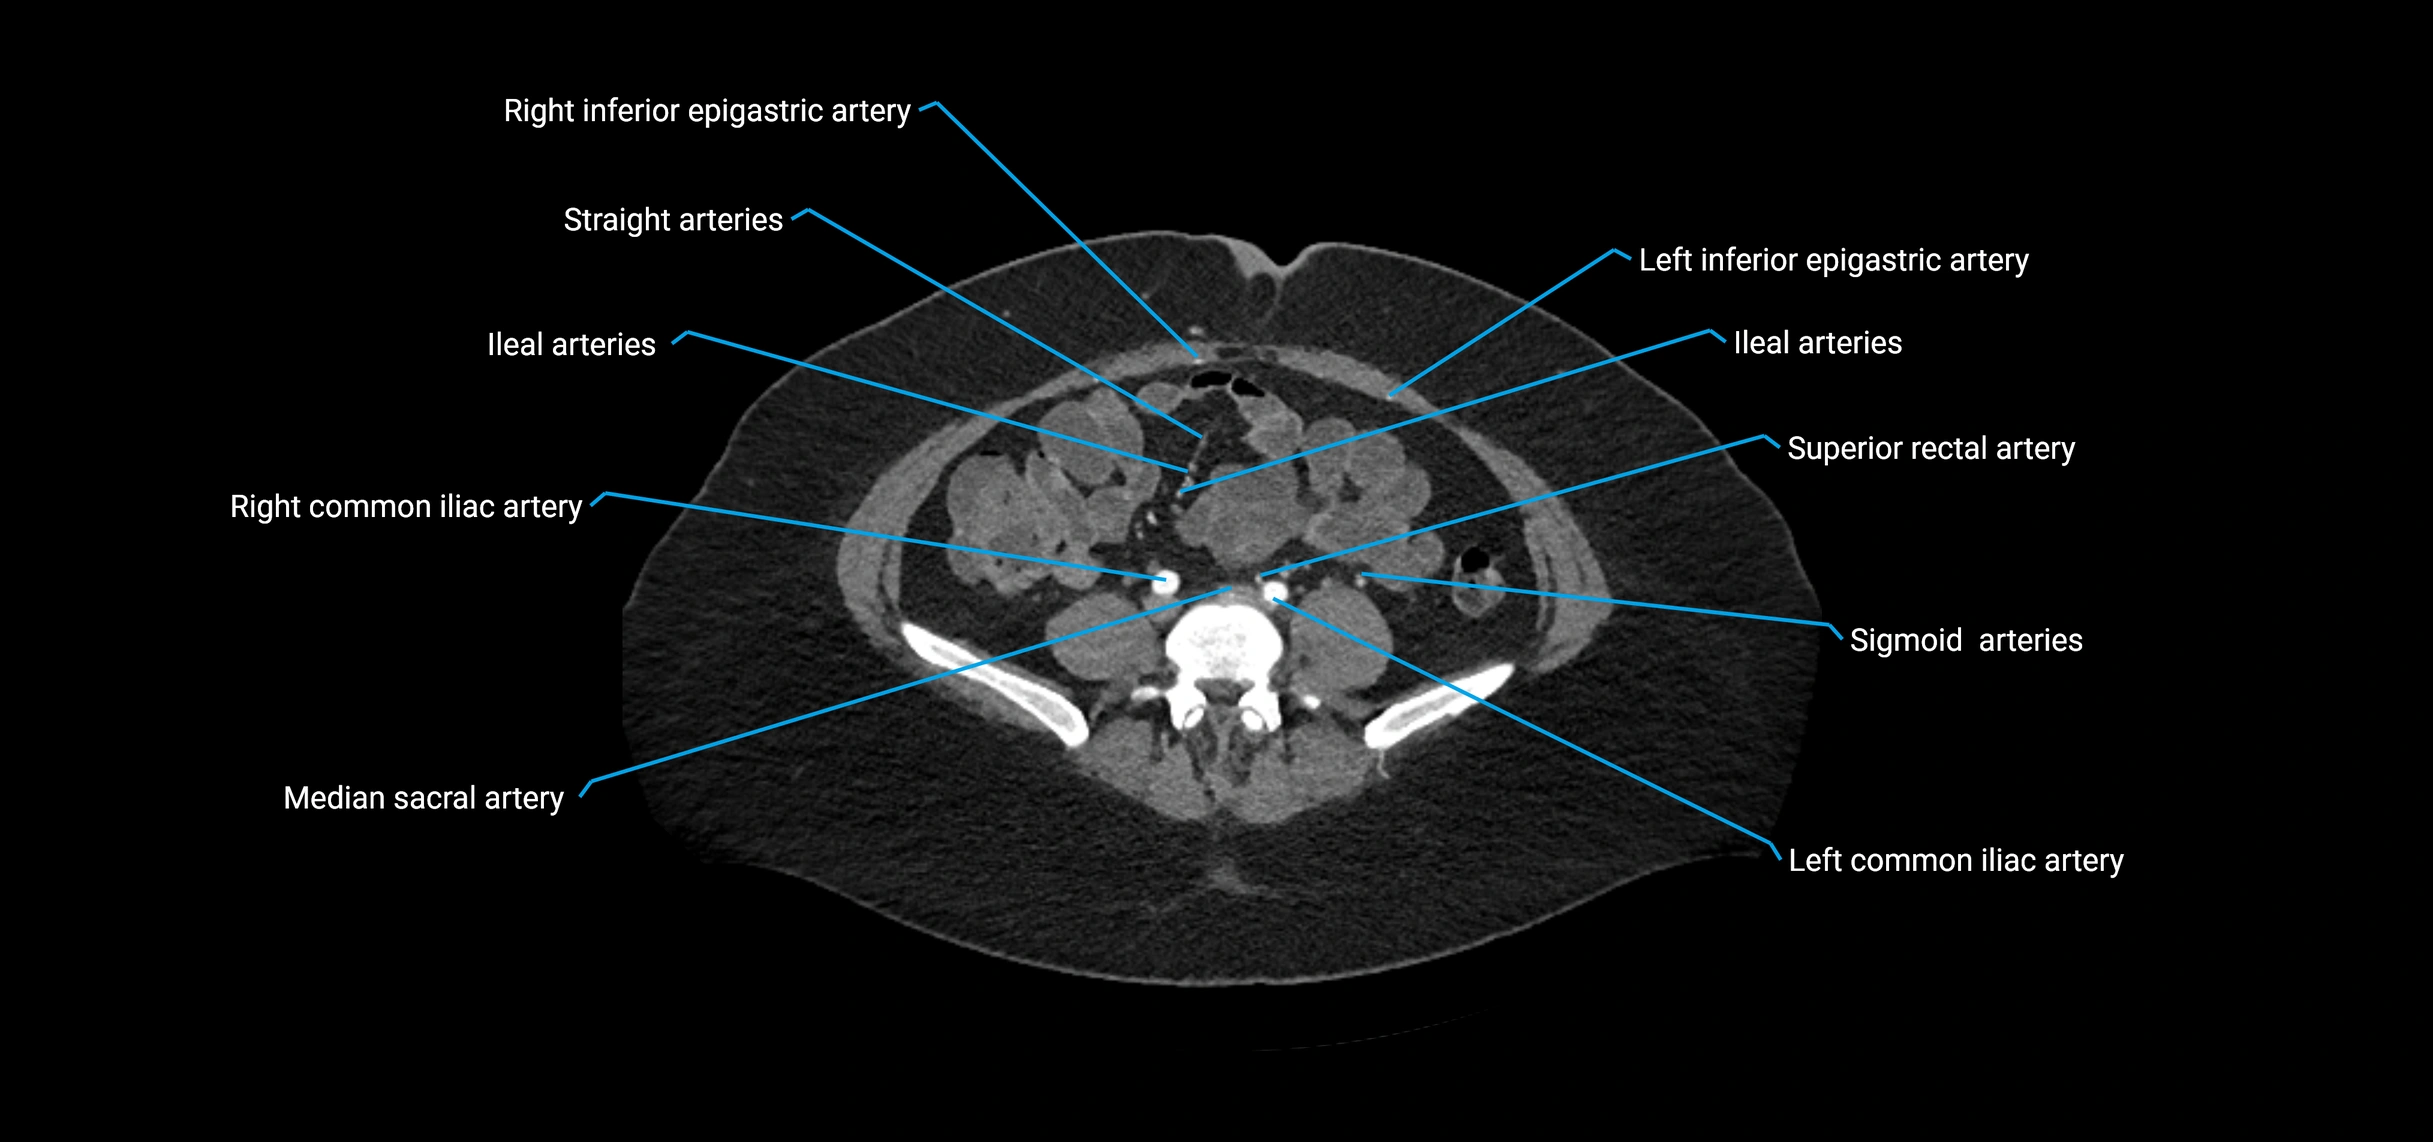

Contrast-enhanced CT (CTA):

• Gold standard for abdominal aortic imaging

• Provides excellent detail of lumen, wall, aneurysm, thrombus, and branch vessels

• Multiplanar and 3D reconstructions help in aneurysm measurement, stent graft planning, and dissection evaluation